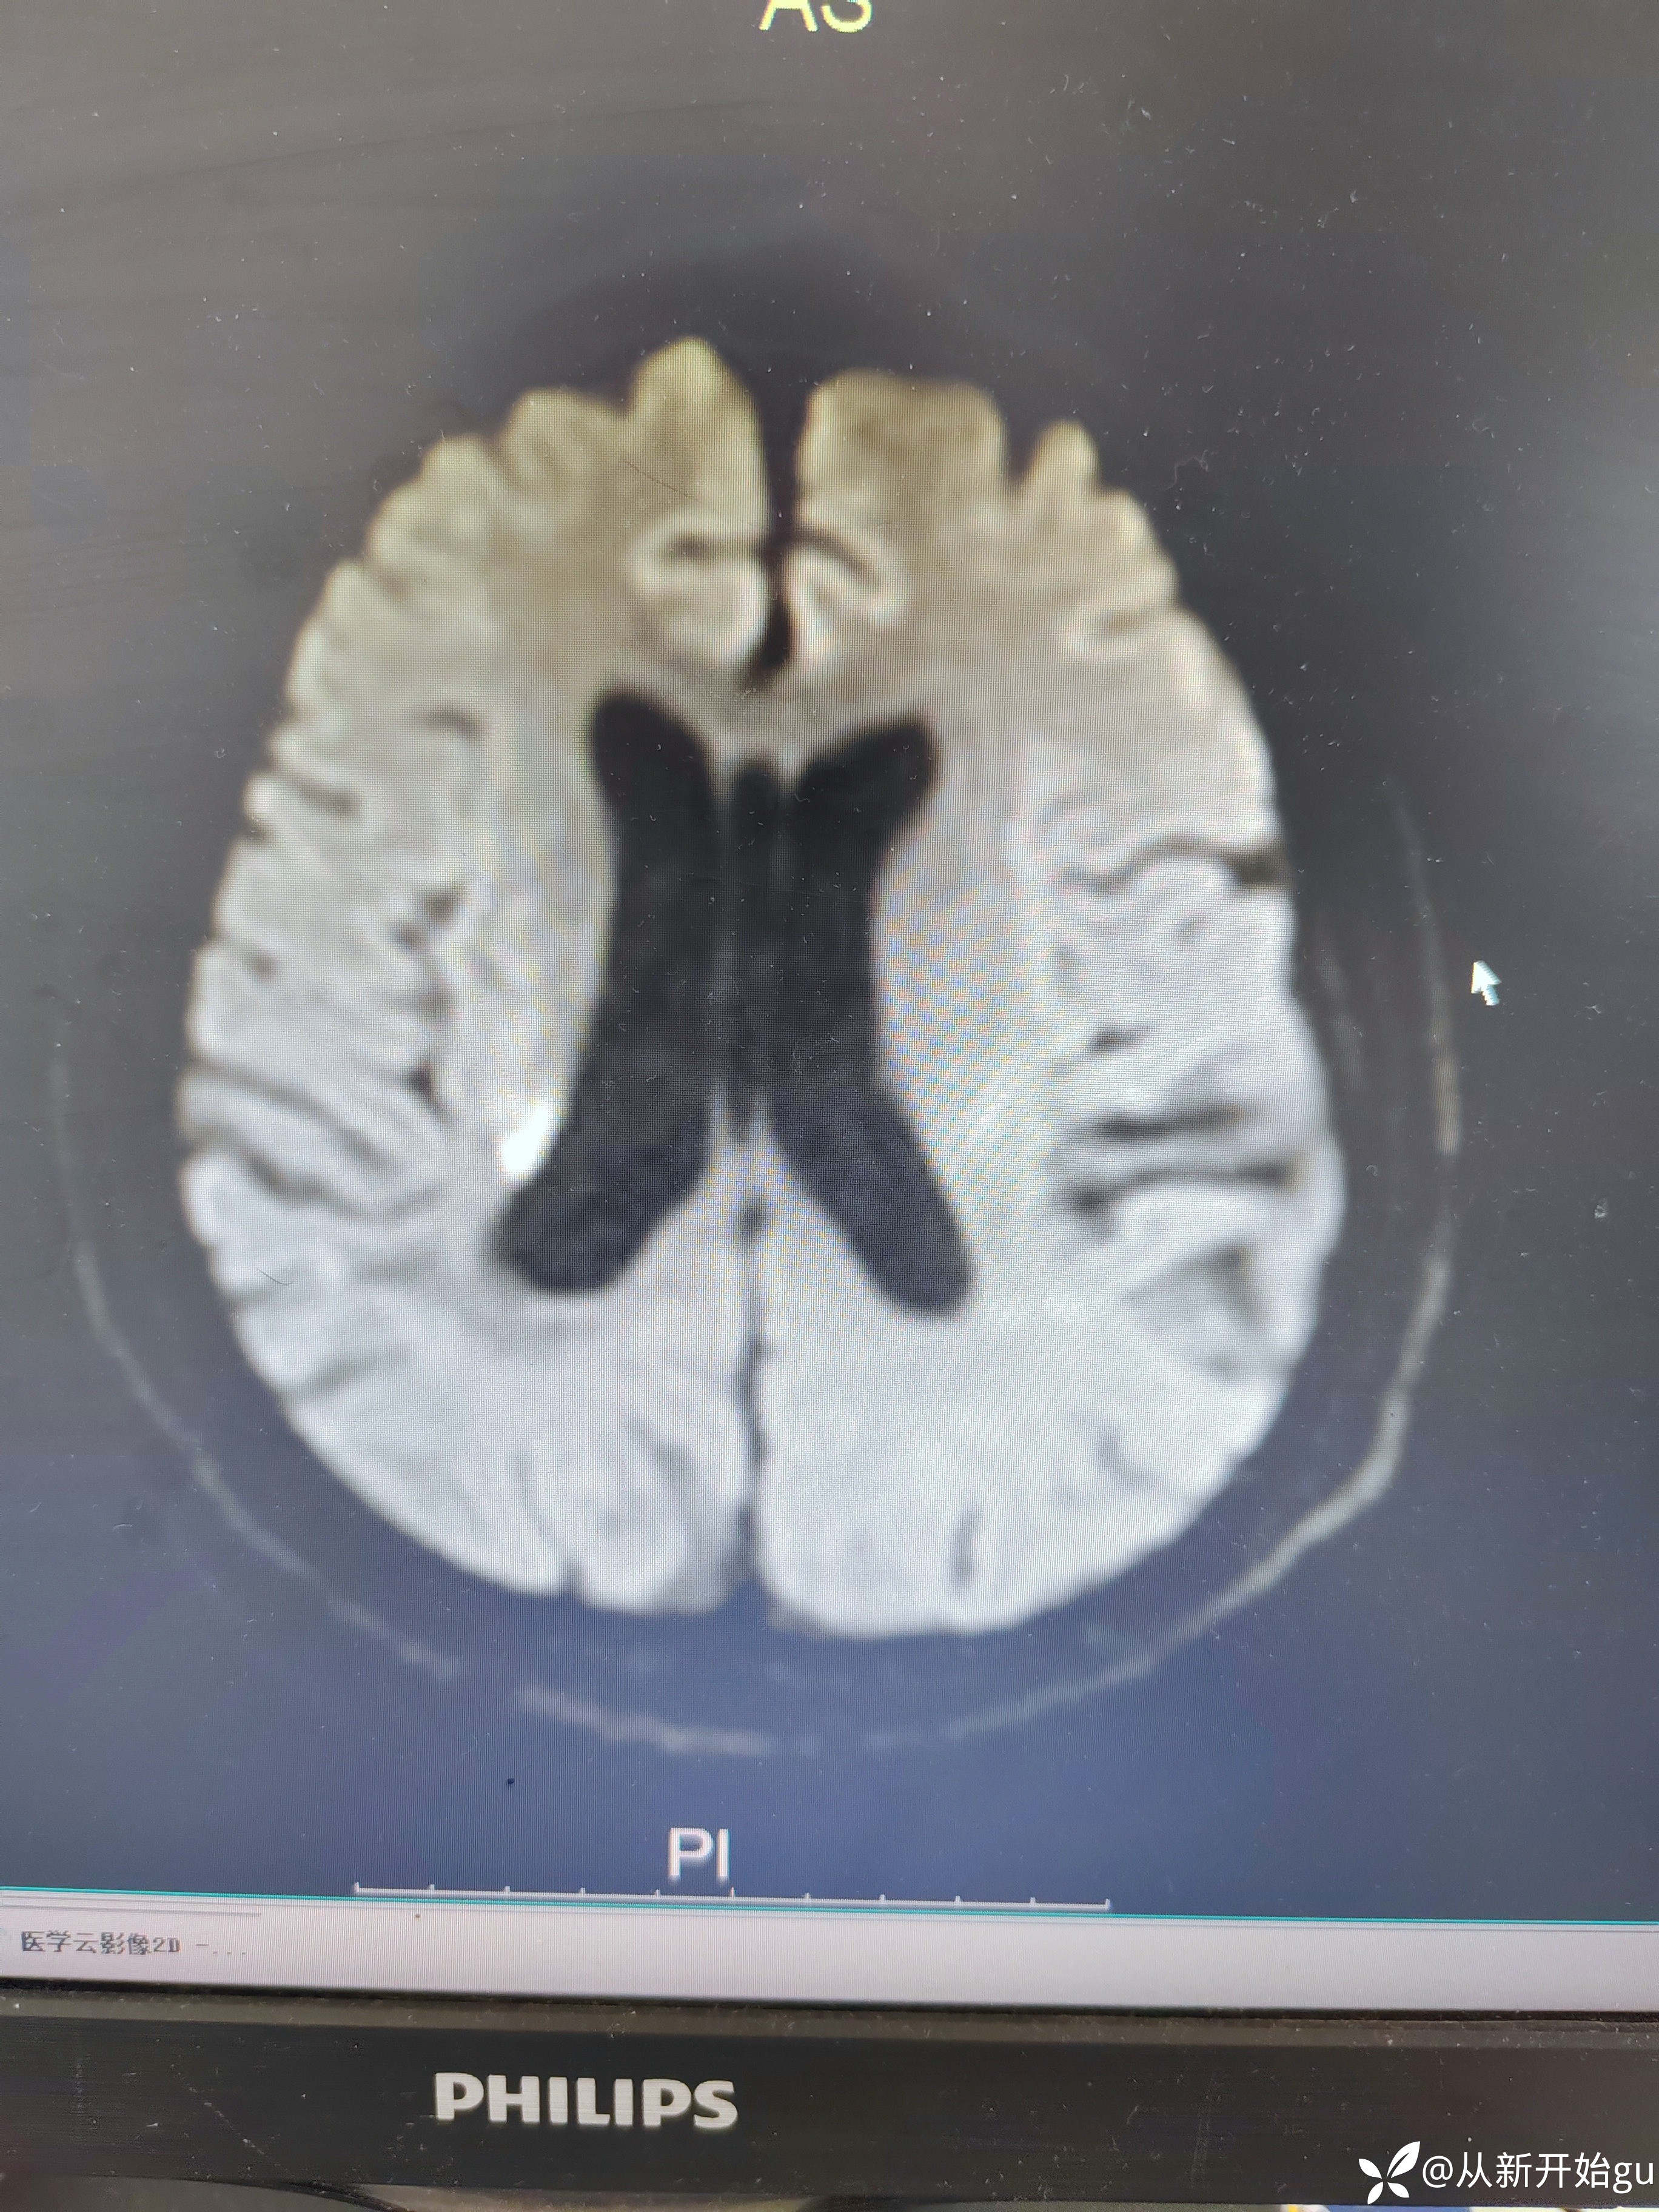

患者男性53岁,主因被发现左下肢活动障碍2.5小时来院,(患者下夜班,于上午9点休息,下午3点醒后出现症状)。既往脑梗死病史9个月,遗留言语不利及口角歪斜的症状。查体:右侧鼻唇沟稍浅,神舌右偏,左侧下肢肌力4级,左侧指鼻试验欠稳准,左侧巴氏征阳性。外院完善颅脑CT无出血改变。来院后完善核磁检查如图所示。